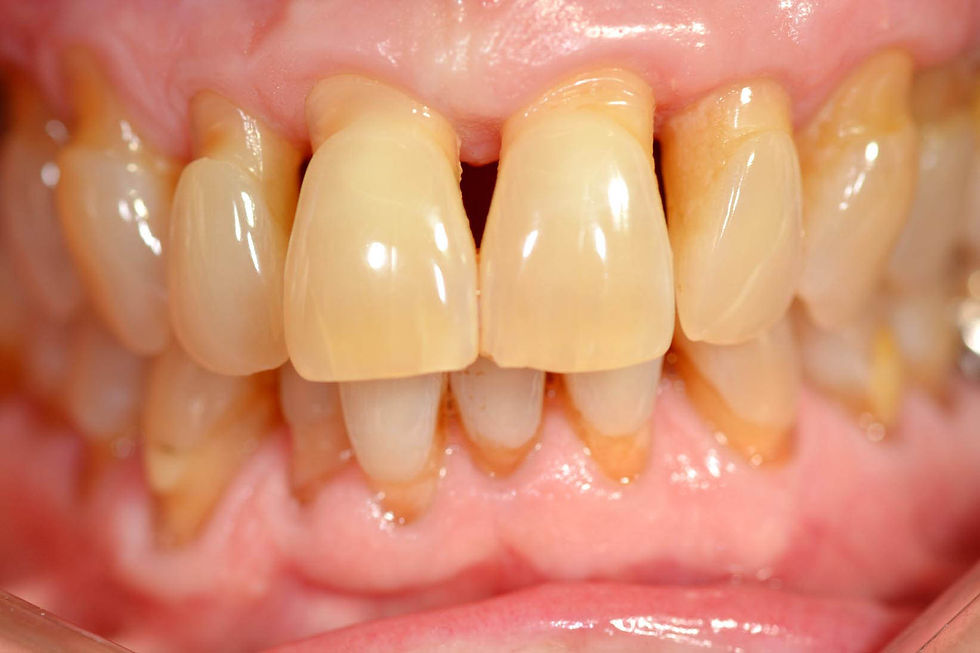

Clinical pre-operative intraoral images that show the vestibular migration of the natural teeth.